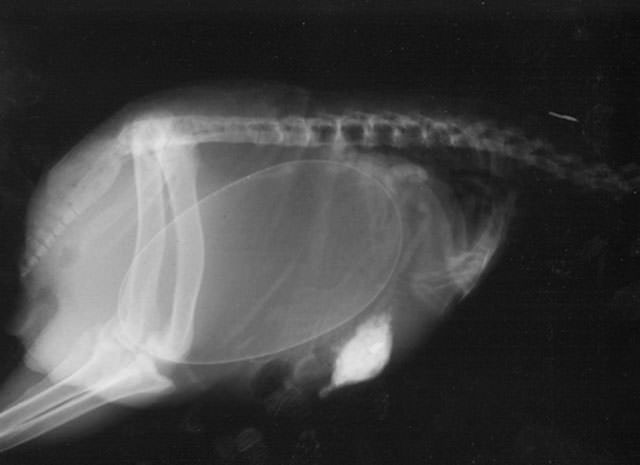

İnsanların ultrason görüntülerini görmeye hepimiz alışkınız. Ancak hamile hayvanların ultrason görüntüleri sizleri çok şaşırtacak.Kaplumbağa

İnsanların ultrason görüntülerini görmeye hepimiz alışkınız. Ancak hamile hayvanların ultrason görüntüleri sizleri çok şaşırtacak.